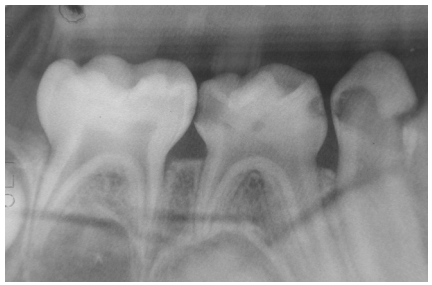

53.下圖所示對於3歲半男孩右下第一乳臼齒的治療選擇,何者並不合適? (A)Indirect pulp therapy and stainless steel crown (B)Indirect pulp therapy and composite restoration (C)Pulpotomy and stainless steel crown (D)Pulpectomy and stainless steel crown

35.下列何者不是急性淋巴球性白血病(acute lymphoblastic leukemia)的症狀? (A).牙艱瘀斑(gingival petechiae ) (B).淋巴腺病(lymphadenopathy ) (C).骨頭疼痛(bone pain) (D).皮疼(skin rash )